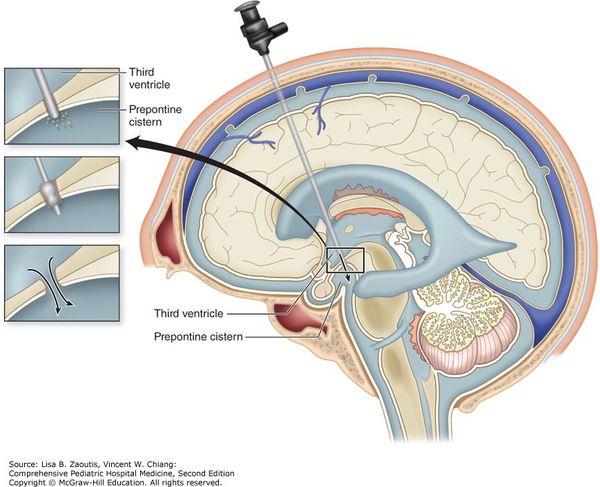

Вентрикуло-перитонеальный шунт: Показания и применение

Раздел: Фотоальбом решений